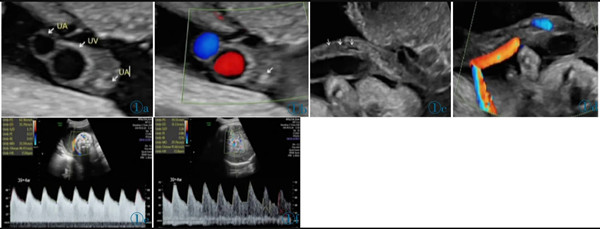

11 例中孕期超聲均可見2 條UA(膀胱水平橫切面顯示2 條UA 血流信號),超聲最后一次提示可見2 條UA 的平均孕周為(31.2±3.1)周。11 例超聲首次提示UA 數(shù)目異常(表現(xiàn)為膀胱水平橫切面UA彩色多普勒僅顯示1 條UA 及血流信號,另一側(cè)血流信號消失)的平均孕周為(36.7±2.8)周,6 例(54.4%)為膀胱左側(cè)血流信號消失,5 例(45.5%)為膀胱右側(cè)血流信號消失。7 例(63.6%)孕晚期超聲首次即提示單條UAT,這7 例臍帶游離段橫切面二維灰階圖像均顯示3 個管腔結(jié)構(gòu),其中1 條UA 內(nèi)可見稍高回聲填充且血流信號消失(圖1);1 例(9.1%)在孕34+4周提示單臍動脈,在孕37 周超聲隨訪中糾正診斷為單條UAT,因超聲提示臍帶高度螺旋,且在臍帶橫切面下見臍靜脈呈“C 形”包繞2條UA,1 條UA 內(nèi)存在血栓回聲(圖2),該病例同時合并胎兒生長受限;3 例(27.3%)整個孕期均提示單臍動脈,回顧其既往中孕期超聲均見2 條UA,晚孕期超聲發(fā)現(xiàn)1 條UA 內(nèi)存在血栓回聲(圖3)。

圖1a 臍帶橫切面。1 條臍靜脈管腔大,內(nèi)為無回聲。2 條UA 管腔小,栓塞側(cè)內(nèi)為稍高回聲(血栓回聲),通暢側(cè)內(nèi)為無回聲。圖1b 臍帶橫切面。臍靜脈及通暢側(cè)UA 內(nèi)見方向相反的血流信號,栓塞UA內(nèi)無血流信號(箭頭所示)。圖1c 臍帶縱切面。臍靜脈內(nèi)為無回聲,栓塞UA 內(nèi)等回聲為血栓(箭頭所示)。圖1d 臍帶縱切面。臍靜脈內(nèi)可見血流信號,栓塞UA 內(nèi)無血流信號。圖1e 通暢側(cè)UA:舒張末期血流流速增加,S/D 和PI 偏低。圖1f MCA:舒張末期血流流速增加,PI 值降低。Figure 1a.Cross section of cord.No echo is shown in the lumen of umbilical vein(the larger one).Two UAs have smaller lumens,and hyperecho is found in the occluded UA(thrombus).Figure 1b.Cross section of cord.Opposite blood flows are shown in umbilical vein and the normal UA,and no blood flow signal is shown in the occluded UA(as indicated by the arrow).Figure 1c.Longitudinal section of cord.There is no echo in umbilical vein and the arrow indicates the thrombus in the occluded UA.Figure 1d.Longitudinal section of cord.There is blood flow in umbilical vein and no blood flow in the occluded UA.Figure 1e.The unobstructed UA: the end diastolic blood flow velocity increases;S/D and PI decreases.Figure 1f.MCA: the end diastolic blood flow velocity increases;PI decreases.

圖2 a 臍帶橫切面。臍靜脈呈“C 形”包繞2 條UA,1 條UA 內(nèi)存在血栓回聲(T:血栓)。圖2b~2d 臍帶高度螺旋。Figure 2 a.Cross section of umbilical cord.One clogged UA is in parallel with the other unobstructed one and both of them are surrounded by umbilical vein(T: thrombi).Figure 2b~2d.Hyper-coiling of umbilical cord.

圖3 誤診為單臍動脈病例的超聲圖像。圖3a:孕24+4 周,膀胱兩側(cè)均可見UA 血流信號;圖3b:孕37+1 周,膀胱一側(cè)UA 血流信號消失;圖3c:臍帶橫切面見臍靜脈呈“C 形”包繞2 條UA,箭頭所示其中1 條UA 管腔細小,內(nèi)為稍高回聲(血栓)填充。圖4 臍帶病理(HE 染色)。UA 內(nèi)見血栓形成,管壁彈力纖維梗死。Figure 3.Ultrasonography misdiagnosed as single umbilical artery.Figure 3a: At 24+4 weeks,the blood flow of two UAs is seen in both sides of bladder.Figure 3b: At 37+1 weeks,only one UA is seen in the level of bladder.Figure 3c: In the cross section of umbilical cord,two UAs are surrounded by umbilical vein.As indicated by the arrows,one UA has smaller lumen which is filled with a slightly higher echo(thrombi).Figure 4.The pathological finding of umbilical cord (HE stain).The UA lumen is filled with thrombi.The necrosis of elastic fibers are found in arterial wall.

4 例(36.4%)UA-S/D 介于相應(yīng)孕周參考值的10 th~<25 th,2 例(18.2%)5 th~<10 th,5 例(45.5%)<5 th。11 例UA-PI 均<相應(yīng)孕周參考值的5th(圖1e)。3 例測量了MCA 血流參數(shù),其中2 例MCAPI<相應(yīng)孕周參考值的5 th(圖1f),這3 例CPR 均無異常。